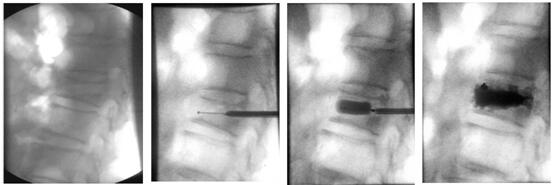

下面帶大家了解椎體成形術(shù)是怎樣做的!

患者俯臥位在手術(shù)床上,透視標(biāo)記骨折椎體;

穿刺點(diǎn)局部麻醉,根據(jù)定位將穿刺錐穿入骨折椎體;

透視確定穿刺錐進(jìn)入骨折椎體后,建立工作通道;

等待15分鐘骨水泥凝固硬化,手術(shù)結(jié)束。病人即刻疼痛消失,術(shù)后第一天可以下床活動(dòng)。